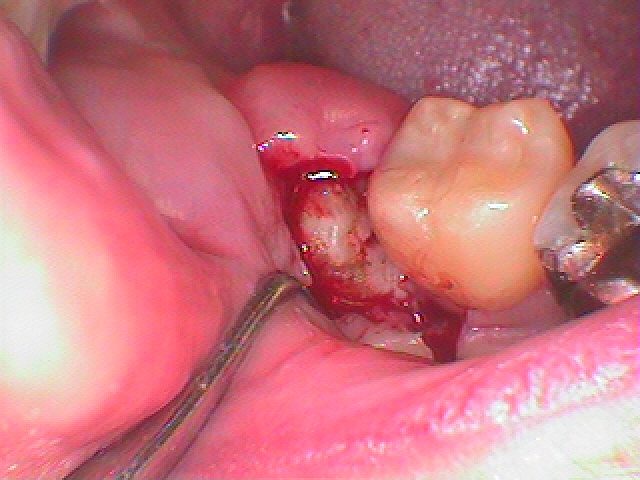

親不知の完全水平埋伏歯抜歯。